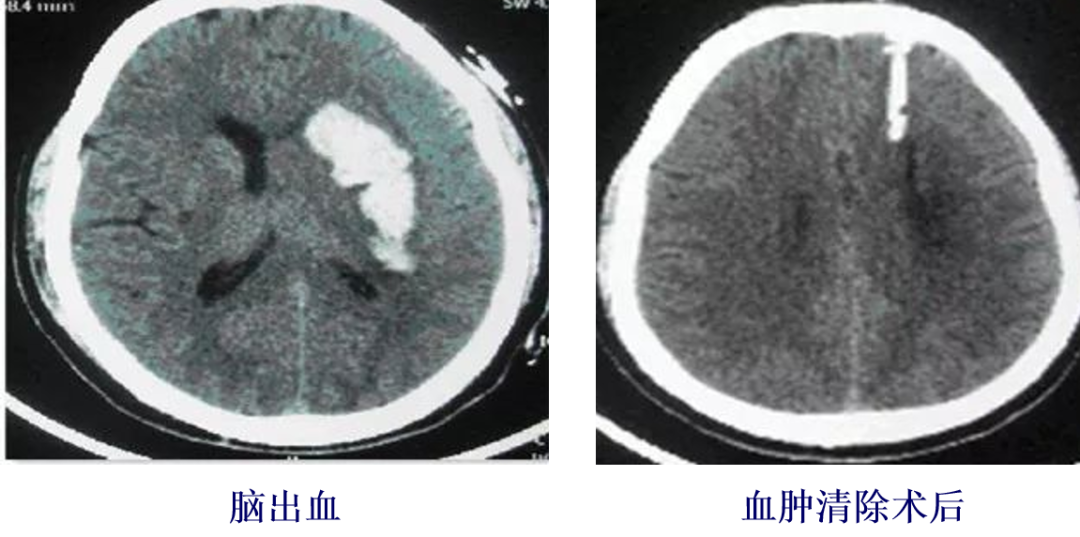

术后恢复:活动自如,但在如厕时突发头痛、呕吐,随后发生脑出血,进行了血肿清除术。